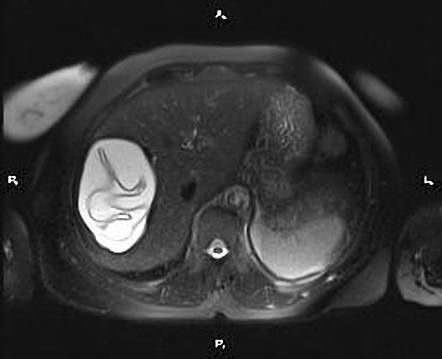

Water-lily sign AKA Camalote sign is a characteristic feature found on imaging in hydatid cyst. It is formed by detachment of endocyst membrane which floats within the cyst. Reference: https://radiopaedia.org/articles/water-lily-sign-hydatid-cyst#:~:text=The%20water%2Dlily%20sign%2C%20also,appearance%20of%20a%20water%20lily. Image via: https://radiopaedia.org/articles/water-lily-sign-hydatid-cyst